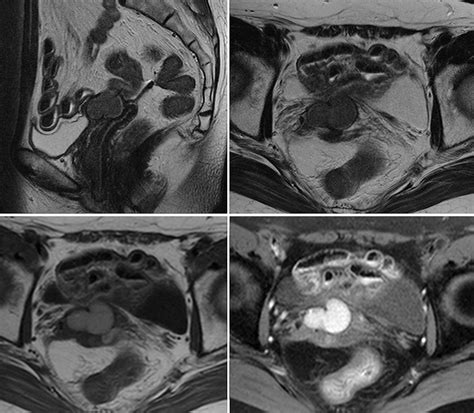

• Imaging Tests: Ultrasound or MRI may be used to confirm the diagnosis and assess the size and location of the cyst.

• vaginal inclusion cyst mri

• vaginal inclusion cyst ultrasound

• vaginal inclusion cyst radiology